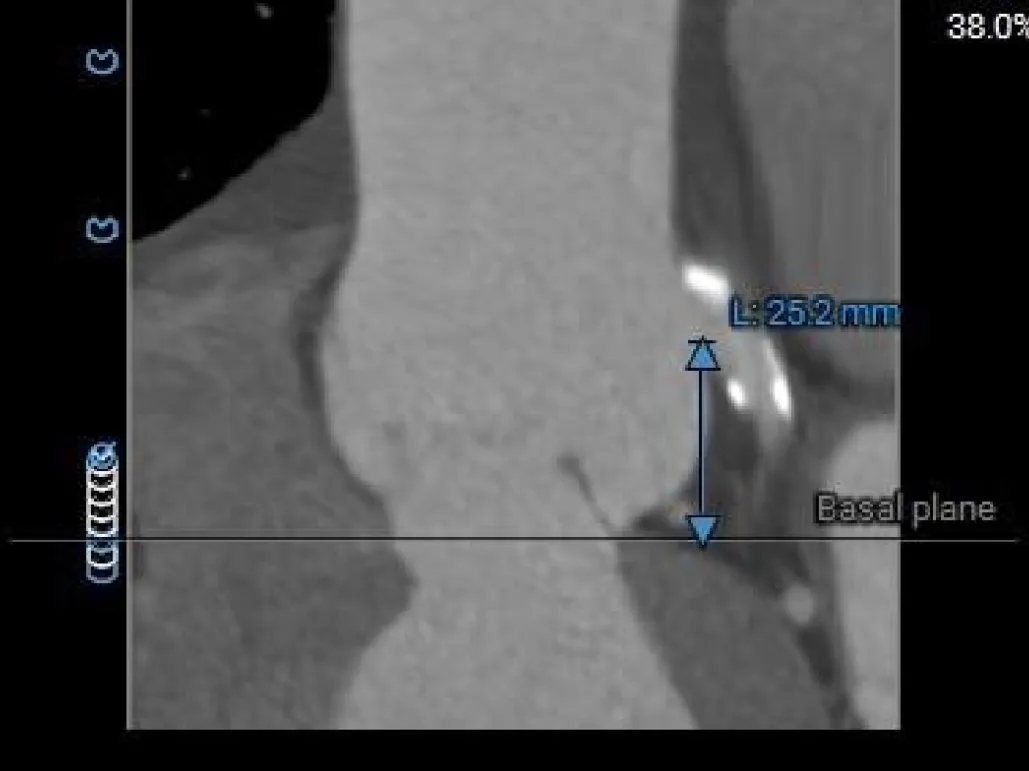

左冠开口高度约为25.2mm,右冠开口高度约为23.2mm;